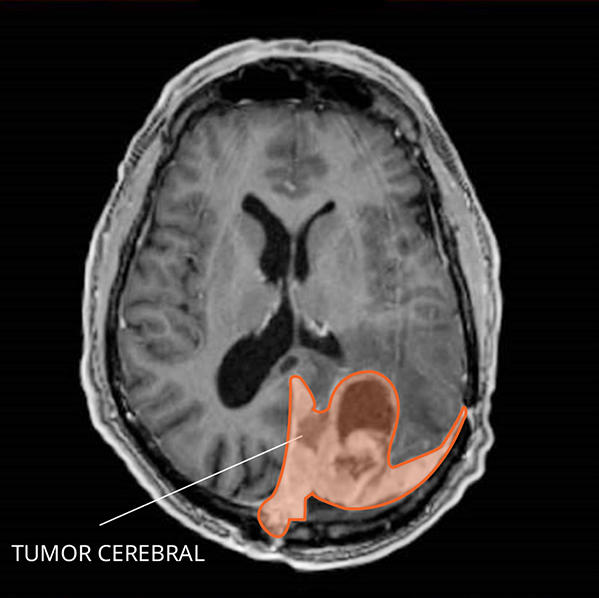

Lista muestra hermosas imágenes de resonancia magnética cerebral normal y anormal dinosenglish.edu.vn para que puedas explorar más en detalle.

resonancia magnética cerebral normal y anormal Pin en NEUROCIENCIAS resonancia magnética de cerebro Resonancia magnética (RM) de cerebro, corte axial ponderado en T2: la … VIDEO Nueva mancha en la Resonancia

Engineer Team : RESONANCIA MAGNETICA Magnetic Resonance Imaging – Clinical Images Hallazgos por resonancia magnética cerebral de nuestro paciente. M, 21 … Imágenes por resonancia magnética anormales como predictoras de mal … Imágenes por resonancia magnética anormales como predictoras de mal … Lesiones en resonancia magnética (RM) del encéfalo y la médula espinal … Pin en Resonancia Magnética del Encéfalo A) Resonancia magnética cerebral (RMC) mostrando infartos en … Caso 1: Edema cerebral visualizado mediante RM. (A) Secuencia T1 plano … Rascacielos dormir pasta tac y resonancia diferencias retrasar … Pin on Apuntes de Enfermería y T.C.A.E Resonancia magnética cerebral secuencia T2, que muestra lesión … Meningitis aguda en la enfermedad de Behçet | Reumatología Clínica Resonancia magnética coronal normal del cerebro Fotografía de stock – Alamy Imágenes de resonancia magnética, la imagen de la cabeza en diferentes … Resonancia magnética cerebral A) protocolo T1 sagital (Caso 1). Se … Resonancia magnética cerebral. Secuencia T1 corte sagital. Atrofia … Resonancia magnética de cerebro, cortes axiales, secuencias T2. Señal … Resonancia magnética de cráneo. A y B) Cortes axiales FLAIR … Resonancia magnética (RM) de cerebro, corte axial ponderado en T2: la … RM cerebral: Interpretación paso a paso | Kenhub Resonancia magnética de cerebro, cortes axiales, secuencias T2. Señal … De Resonancia Magnética De Cerebro Foto de archivo – Imagen de arteria … Top 107+ Imagenes de resonancia cerebral normal – Destinomexico.mx -Imagen por resonancia magnética del cerebro. a) Cortes sagital y axial … resonanCia magnétiCa Cerebral donde se observa hiperintensidad a nivel … MRI (Imagen de resonancia magnética) – Tomografía computarizada de la … Meningioma – NCI Imágenes por resonancia magnética coloreadas del cerebro sano del … Resonancia magnética cerebral en secuencia FLAIR, que muestra lesiones … Contraste resonancia magnetica cerebral – senturinthegreen Relación de los espacios de Virchow-Robin con la enfermedad de … Gliomatosis cerebral – Instituto Nacional del Cáncer Pin en Neurology. Recomendaciones para la utilización e interpretación de los estudios de … Fotografía De La Proyección De Imagen De Resonancia Magnética Del … atmósfera Dirigir Cumplir anatomia resonancia magnetica Desarrollar … Pin en #MEDICINA,#SALUD Resonancia magnética de la nasofaringe De Resonancia Magnética De Cerebro Foto de archivo – Imagen de polilla … Atrofia cortical global de predominio parietal en la Resonancia … Resonancia magnética cerebral | Download Scientific Diagram Neuroblog: Resonancia magnética cerebral en la trombosis crónica de … De Resonancia Magnética De Cerebro Imagen de archivo – Imagen de … ¿Cuáles son los riesgos de la resonancia magnética? – Integra Salud … Resonancia magnética cerebral al decimocuarto día de ingreso: área … Resonancia magnética. Corte axial mostrando área infartada en el … Resonancia magnética cerebral del paciente AV evidenciando lesiones en … -Ressonância magnética de encéfalo mostrando múltiplas imagens … Resonancia magnética cerebral secuencia FLAIR (Fluid Attenuated … Resonancia magnética cerebral con protocolo de epilepsia, en sección … Resonancia magnética cerebral en corte sagital. Se observa una evidente … Resonancia magnética craneal en la que se evidencian lesiones … Logran visualizar el cerebro a detalle más completo tras una resonancia … Así decide el cerebro la severidad de un castigo De Resonancia Magnética De Cerebro, Imagen de archivo – Imagen de … A) Resonancia magnética cerebral; Secuencia Tof: oclusión de arteria … Un estudio asocia la ansiedad con la aparición rápida del Alzheimer IMÁGENES DE 18 F-PR04.MZ PET FUSIONADA CON RESONANCIA MAGNÉTICA … Imágenes por resonancia magnética anormales como predictoras de mal … Tumores de la región pineal – Instituto Nacional del Cáncer Epilepsia: una historia de voces y fantasmas | Neurología Contribución de las imágenes de resonancia magnética por tensor de … Resonancia magnética secuencia T2 plano coronal de quiste epidermoide … Resonancia Magnética Cerebral del paciente: a. Aumento de… | Download … Resonancia magnética cerebral 2022 Síndrome de hemiconvulsión-hemiplejía-epilepsia. Seguimiento de un caso … Enfoque Radiologico: La resonancia magnética permite detectar lesiones … Resonancia magnética craneal T1 con contraste que muestra angiomatosis … guidewiz – Blog Resonancia magnética cerebral, secuencia SWI. Ribete hipointenso en la … resonAnCiA mAgnétiCA de ColumnA Con gAdolinio. Corte sAgitAl en t1 de … SEMANA 12: FUNDAMENTOS DE RESONANCIA MAGNÉTICA NUCLEAR. INDICACIONES Y … DIAGNÓSTICO DE ESCLEROSIS MÚLTIP Magnetic resonance imaging of the brain – Alchetron, the free social … Resonancia magnética de órbitas | Instituto Radiológico Dr. E Castillo Alteración de la marcha en un paciente post-trasplante hepático Resonancia magnética cerebral de un paciente sano (Ay B) y paciente que … Utilidad de la resonancia magnética craneal para el diagnóstico de la … Resonancia Magnética Del Cerebro El Tumor Cerebral Foto de stock y más … De Resonancia Magnética De Cerebro Imagen de archivo – Imagen de … ABDALLA RADIOLOGIA: NEURINOMA ACUSTICO Atrofia cortical global de predominio parietal en la Resonancia … Resonancia Magnética : Producción de la imagen MRI Brain Scan — Stock Photo © Bunyos30 #18724051 Mri (imagen de resonancia magnética) Monitor con imagen de captura de … Tomografía computarizada vs resonancia magnética: diferencia y … Tumores Cerebrales – Unidad de Neurocirugía RGS Resonancia magnética de la columna, sección sagital. Observe los discos … La resonancia magnética, una técnica imprescindible en el diagnóstico … Perfusión Cerebral por Resonancia Magnética | ¿Qué es? ¿Necesita Contraste? Resonancia Magnética Cerebro A: resonancia magnética, T2 coronal preoperatoria; se observa lesión en … Resonancia magnética cerebral — Foto de stock © Bunyos30 #27340623 La resonancia magnética se perfila como detector de mentiras | Futuro … Resonancia magnética cerebral en T1 con gadolinio, cortes axial (a … MRI brain : show brain tumor at right parietal lobe of cerebrum — Stock … NEUROIMÁGENES EN ENFERMEDAD DE PARKINSON: ROL DE LA RESONANCIA …